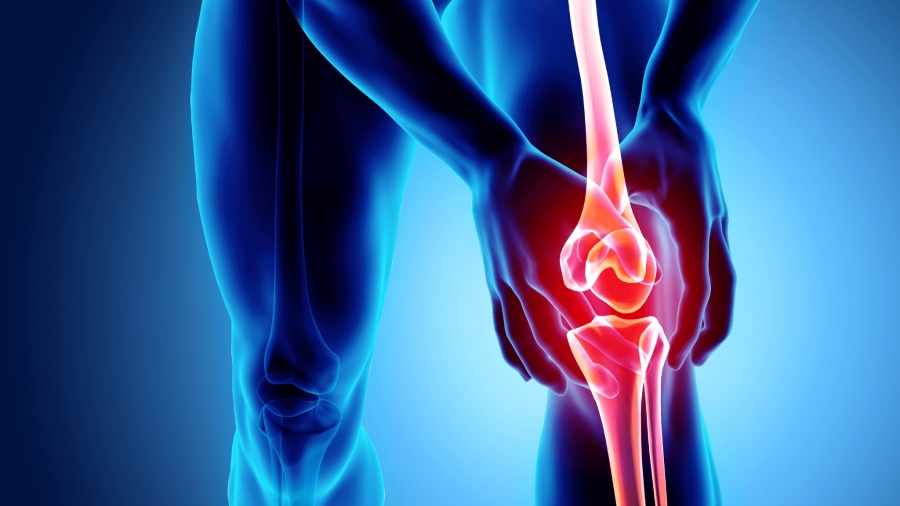

Ο πόνος στο γόνατο (οξύς ή χρόνιος) είναι από τα συχνότερα προβλήματα, που ταλαιπωρούν τους ανθρώπους όλων των ηλικιών.

Ο πόνος στο γόνατο (οξύς ή χρόνιος) είναι από τα συχνότερα προβλήματα, που ταλαιπωρούν τους ανθρώπους όλων των ηλικιών.

Οι περισσότεροι από εμάς, όταν επισκέπτονται τον Ορθοπαιδικό, έχουν στο μυαλό τους ότι το πρόβλημα που αντιμετωπίζουν μπορεί να λυθεί με χάπια, ενέσεις, φυσικοθεραπείες ή έστω με ένα «μαγικό ραβδάκι», οτιδήποτε δεν περιλαμβάνει τον όρο «χειρουργείο». Ωστόσο, υπάρχουν παθήσεις, (ρήξεις μηνίσκων/ χιαστών, οστεοαρθρίτιδα) που, ή δεν μπορούν να επιλυθούν με τους παραπάνω τρόπους, ή έχουν εξαντληθεί από χρόνια, όλοι οι τρόποι συντηρητικής αντιμετώπισής τους, χωρίς ανταπόκριση πια. Μία χειρουργική επέμβαση, συνήθως, δεν είναι και η πιο αποδεκτή λύση, για όποιον αντιμετωπίζει πρόβλημα στο γόνατό του.

Αρθροσκόπηση: μια εξαιρετικά ατραυματική επέμβαση

Όσον αφορά στο αμιγώς ορθοπαιδικό-χειρουργικό κομμάτι, οι εξελίξεις τα τελευταία χρόνια είναι τόσο μεγάλες, που έχουν ανατρέψει όλα όσα έχει ακούσει ή φαντάζεται ο καθένας. Συγκεκριμένα, η αρθροσκόπηση είναι εξαιρετικά ατραυματική επέμβαση, με ταχύτατη αποκατάσταση και ελάχιστο χρόνο νοσηλείας. Ο χρόνος διάρκειας του χειρουργείου, δεν ξεπερνά, τα 30-40 λεπτά. Μετά την επέμβαση, ο ασθενής δεν χρειάζεται πατερίτσες ή νάρθηκες, ενώ φεύγει την ίδια ημέρα, επιστρέφοντας στο σπίτι του και την καθημερινότητά του. Το αισθητικό δε αποτέλεσμα, είναι άψογο, αφού οι οπές που γίνονται για την αρθροσκόπηση είναι της τάξης των 5 χιλιοστών και σχεδόν δεν διακρίνονται.

Αρθροπλαστική του γόνατος

Η αρθροπλαστική του γόνατος γίνεται πλέον με μικρή τομή και ελάχιστη επεμβατικότητα, και μπορεί να συνδυαστεί με κάποιο ρομποτικό σύστημα, με αποτέλεσμα ο ασθενής να μην έχει πόνους και αιμορραγία. Μετά από νοσηλεία δυο ημερών, επιστρέφει στο σπίτι του περπατώντας, ενώ η αποκατάστασή του είναι ταχεία και η ποιότητα ζωής του εξαιρετική. Ακόμη και το αισθητικό αποτέλεσμα, μετά από μία χειρουργική επέμβαση στο γόνατο, με τις σύγχρονες minimal τεχνικές, είναι ασυγκρίτως καλύτερο από το αντίστοιχο με τις παλιότερες χειρουργικές τεχνικές.